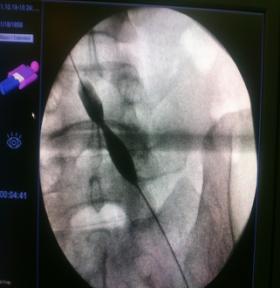

急诊造影:小腿深静脉通畅,腘静脉通畅,见图2

图2